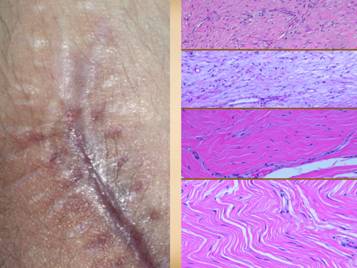

Left upper:  rheumatoid, ulceration over and into small joints.  Left center:  rheumatoid, ulceration along old scar.  Left lower:  scleroderma, livedo reticularis, ulceration along tendons (this ulcer is not under the metatarsal heads).  Left inner:  rheumatoid, ulceration along old scar and tendon.  Right inner upper:  rheumatoid, ulceration in unusual area along tendons (thigh, hamstrings).  Right inner lower:  lupus-mctd, atrophie blanche dermal scarring.  Right upper:  rheumatoid, wound failure of unlikely location (abdomen).  Right lower:  rheumatoid and hypercoagulable, wound failure of unlikely location (forearm), ulceration along muscle and tendon, necrosis around staples.

Whether looking at the prodrome, acute, or chronic phases, many of the wound features are generic findings of any inflammation, thrombosis, or ulceration.  However, immunopathic ulcers can have some very distinctive features unlike wounds from other primary diagnoses.  Many of these reflect specific effects of the given primary disease, such as necrotizing synovitis from rheumatoid and lupus, and skin sclerosis and calcification from scleroderma.  These features include:  ulceration along tendons, due to synovitis;  inflammation, lysis, ulceration of old scars;  ulceration over small joints, due to synovitis;  inflammation, lysis, necrosis along recent incisions;  ulceration of the upper leg outside of the gaiter area, and ulceration in a variety of other areas;  skin atrophy in affected areas, due to persistent inflammation and proteolysis;  skin sclerosis in affected areas due to scarring after inflammation;  vascular changes in skin and extremity;  wound pathergy, necrosis, and ulceration after injury and surgery;  calcification and ossification in the ulcers or surrounding panniculus.